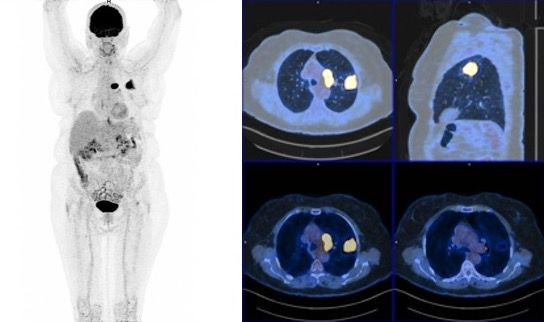

In an asymptomatic 77-year-old woman, former 55 pack-years smoker, a routine X-ray showed a 45-mm superior left lobe lesion (Figure 1). A chest CT scan confirmed a 36-mm superior left lobe lesion and an aortic-pulmonary lymph node enlargement measuring 42 mm, suspicious for neoplasia (Figure 2). A PET-CT scan showed an elevated uptake in the primary lesion, in the aortic-pulmonary lymph node, and in the left hilar lymph node with a standardized uptake value – 40 and 4.3, respectively (Figure 3).

Figure 3. PET-CT with pulmonary and lymph node involvement.